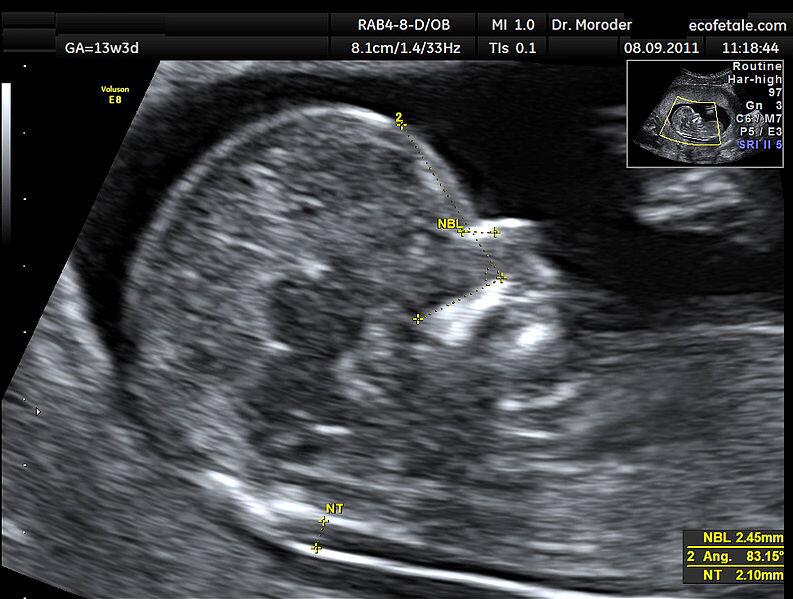

七、正矢位B超图参考

图片来自维基百科的NT超声图

NT是nuchal translucency的简写,翻译成中文是“颈部透明层”的意思,指胎儿颈后皮下组织内液体积聚的厚度。是早期唐氏筛查的重要风险测算项目,也是诊断染色体疾病和心脏问题、其他畸形问题等非染色体问题的重要筛查依据,是整个孕期的大排畸检查中的首次排畸检查。

NT检查的正常值在不同地区不同医院都的标准都会有所差异,奶爸目前所知的就有2.5mm、3.0mm、3.5mm这3个标准。总之,超过正常值,NT越厚,风险就越大。

1、做NT对医生的测量技术要求非常高,稍微有些偏差,就有可能会有零点几毫米的误差。NT增厚,先检查B超图片是不是正矢位,不是正矢位肯定会有误差,建议复查。